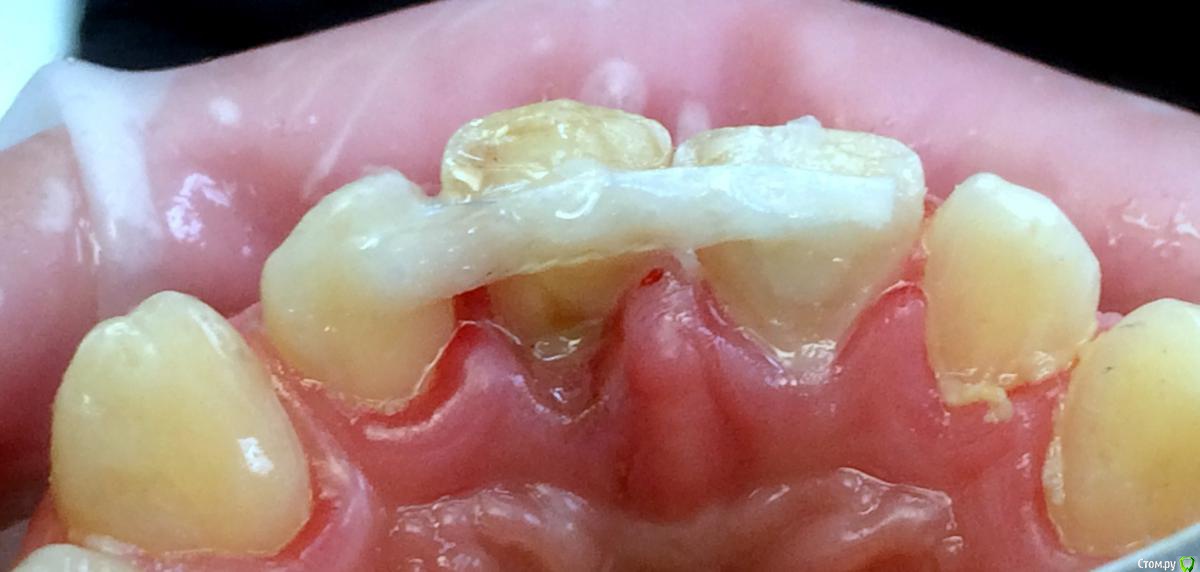

Art 7 Опубликовано 11 августа, 2017 Поделиться Опубликовано 11 августа, 2017 ставишь стекловолоконную балку между апроксимальных поверхностях соседних зубов) Ссылка на комментарий

kamranchick Опубликовано 11 августа, 2017 Автор Поделиться Опубликовано 11 августа, 2017 ставишь стекловолоконную балку между апроксимальных поверхностях соседних зубов)Спасибо Артурчик)Попробуем так))) просто шатается сильно, страшно трогать пока что) Ссылка на комментарий

1586Doc Опубликовано 11 августа, 2017 Поделиться Опубликовано 11 августа, 2017 (изменено) Это обычная силиконовая каппа ?вытягиваем, потом стабилизация ? Как на долго? Изменено 11 августа, 2017 пользователем 1586Doc Ссылка на комментарий

kamranchick Опубликовано 11 августа, 2017 Автор Поделиться Опубликовано 11 августа, 2017 Это обычная силиконовая каппа ?вытягиваем, потом стабилизация ? Как на долго?капу сделали вакуум формером, помоему она пластмассовая вроде. стабилизация 2-3 месяца... Ссылка на комментарий